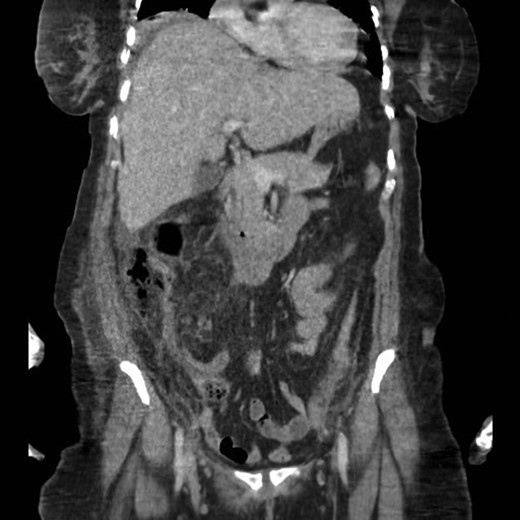

A CT scan revealed an appendix with an enhanced oedematous wall, adjacent retroperitoneal subhepatic air and mild collection indicative of a perforated subhepatic appendix (Fig. 1).

A second abdominal CT scan showed an ill-defined retroperitoneal collection, mainly on the right side. In fact, two pockets of collection in the right retroperitoneal area were observed: the first pocket was just under the abdominal muscles and peripherally, and the second pocket was just anterior to Gerota’s fascia of the right kidney.